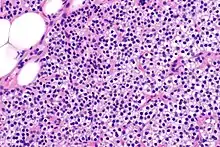

Hyperparathyroidism, in general, is caused by either tumorous growth in one or more parathyroid glands or a prolonged decrease in blood calcium levels or hypocalcaemia which in turn stimulates the production of parathyroid hormone release from the parathyroid gland.[10][11] The parathyroid gland is located beside the thyroid gland in the neck, below and in front of the larynx and above the trachea. It is composed of four glands in total that monitor blood calcium levels via the calcium sensing receptors, a g-coupled protein receptor.[12] The parathyroid glands main role is calcium homeostasis.[13][12] Histologically, these glands are composed of chief cells and oxyphil cells with the chief cell primarily responsible for the storing and release of parathyroid hormone. These cells are arranged in a pseudo-follicular pattern similar to the thyroid follicles. Keratin staining is used to image the parathyroid hormone granules.[9][14]

Primary hyperplasia of the parathyroid gland, results from both hypocalcaemia and increased phosphate levels by decreasing expression of calcium sensing receptors and vitamin D receptors at the parathyroid gland.[8][4] These decreases in receptor expression lead to hyperfunctioning of the parathyroid. Hyperfunction of the parathyroid gland is thought to exacerbate primary hyperplasia which evolves further to a secondary more aggressive hyperplasia. Histologically, these hyperplasic glands can be either diffuse or nodular.[24] Primary hyperplasia, usually resulting in diffuse polyclonal growth is manly related to reversible secondary hyperparathyroidism. Secondary hyperplasia of the parathyroid gland is more often a nodular, monoclonal growth that sustains secondary hyperparathyroidism and is the catalyst in the progression to tertiary hyperparathyroidism. Nodular hyperplastic glands in tertiary hyperparathyroidism are distinctly larger in both absolute size and weight up to 20-40-fold increases have been reported.[25][26][24]

Parathyroid glands are normally composed of chief cells, adipocytes and scattered oxyphil cells.[27][14] Chief cells are thought to be responsible for the production, storage and secretion of parathyroid hormone. These cells appear light and dark with a prominent Golgi body and endoplasmic reticulum. In electron micrographs, secretory vesicles can be seen in and around the Golgi and at the cell membrane. These cells also contain prominent cytoplasmic adipose.[27][14] Upon onset of hyperplasia these cells are described as having a nodular pattern with enlargement of protein synthesis machinery such as the endoplasmic reticulum and Golgi. Increased secretory vesicles are seen and decreased intercellular fat is characteristic.[27][24] Oxyphil cells also appear hyperplasic however, these cells are much less prominent.